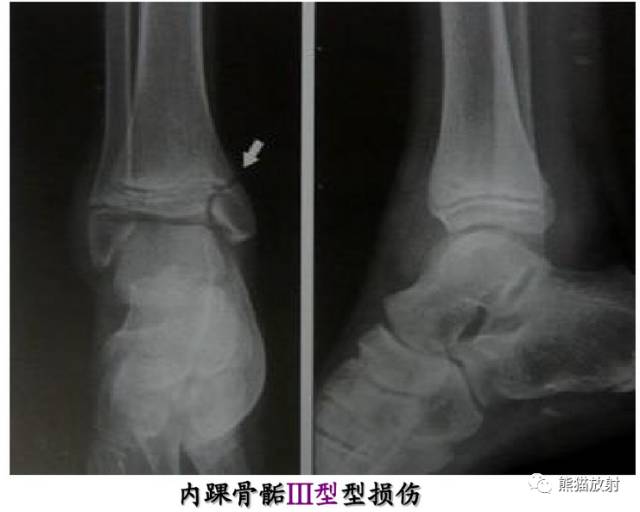

III型:骨骺骨折(属于关节内骨折)

Salter-Harris III型:骨折累及骺板及骨骺,属于关节内骨折,可导致生长停滞。

第三型(Ⅲ型) 骨骺骨折。属于关节内骨折,骨折线从关节面开始穿过骨骺,再平行横越部分骺板的肥大层。该型占骨骺损伤的4%。多发生在胫骨远端内侧或外侧和肱骨远端外侧。无移位关节面平整者预后良好,有移位者需切开复位内固定,—般移位超过2mm者既是切开复位内固定的适应证。